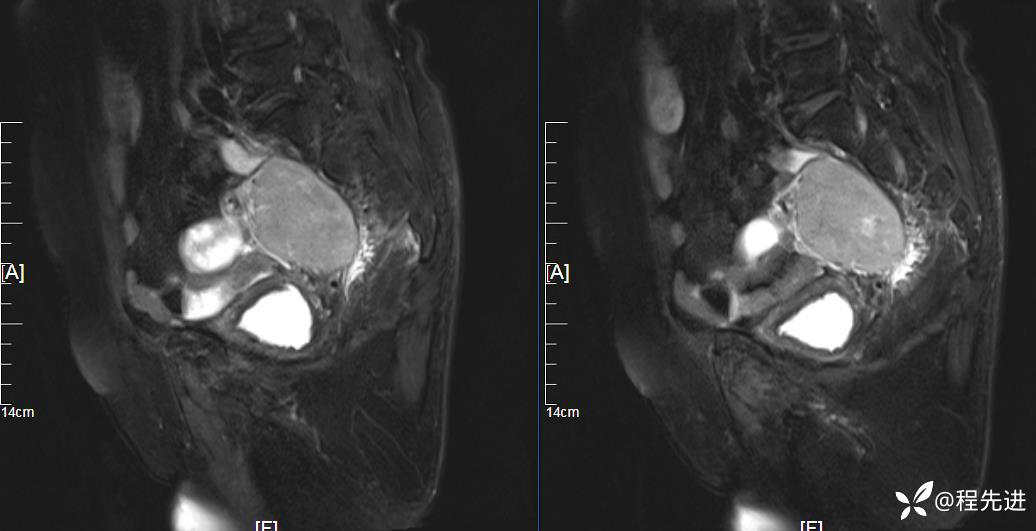

MRI平扫: